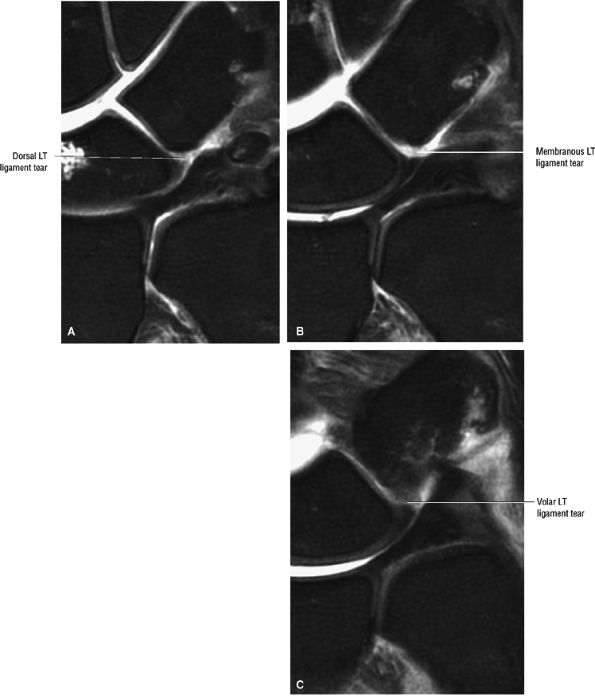

FIGURE 10.35 LUNOTRIQUETRAL LIGAMENT.

|